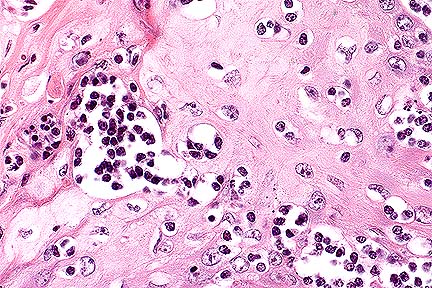

Mild to moderate non-suppurative myelitis with axonal swelling and degeneration. There is accumulation of amyloid protein around the vessel seen here in longitudinal section. (HE, 200X, 56K)

Cross section of a vessel whose wall is largely effaced by amyloid. The myelitis is very prominent in this photomicrograph. (HE, 200X, 63K)

Contributor's Diagnosis and Comments: In locally extensive areas of the spinal cord (S1), corresponding to the areas where the gross lesions were identified, there are large numbers of lymphocytes and macrophages, with local infiltrates of neutrophils and isolated eosinophils surrounding leptomeningeal vessels and extending into the subjacent neuropil of both the grey and white matter. Vessel walls, within both the white and grey matter, are infiltrated and surrounded by concentric accumulations of an eosinophilic, amorphous material which shows apple-green birefringence under polarized light after Congo-red staining (amyloid). Within some sections, there is an extensive accumulation of amyloid surrounding the central canal. There is intense gliosis of both white and grey matter. Within the white matter there is extensive, multifocal axonal degeneration and large numbers of axon sheaths containing gitter cells. Within the grey matter there is neuronal satellitosis and neuronal degeneration and necrosis characterized by swollen neurons which show extensive chromolysis. Multifocally, within the meninges there are moderate perivascular accumulations of lymphocytes and plasma cells with smaller numbers of neutrophils (not evident in all sections).

The most severe necrotizing and inflammatory lesions with perivascular amyloid are centered around T1 and T2; however, a gradation of inflammatory lesions extends from C5-T4. A second small, less severe, focus of myelitis, which unilaterally involves the left ventral grey horn and extends into the white matter, is also present at L1-L2.

The lesions in the spinal cord are consistent with protozoal myelitis (Sarcocystis neurona); however, no protozoal cysts or individual zoites could be definitively identified in the sections examined. This may be the result of the extensive long term therapy with a folic acid antagonist. The extensive accumulation of perivascular amyloid in the spinal cord is a very unusual lesion. Cerebral perivascular amyloid is described in old dogs and is associated with neuronal senile plaques. The cerebral amyloid deposits in old dogs are immunoreactive for beta-amyloid protein found typically in human brain from patients with Alzheimer s disease. Spinal cord amyloid angiopathy has been described in the human literature but is considered a rare and unusual lesion. Amyloid deposition, usually of the AA type (serum amyloid protein), is not uncommonly found in other parenchymal organs (liver and kidney) associated with chronic inflammatory diseases, but to our knowledge has not been described in the CNS in horses. The exclusive localization of the amyloid to the areas of spinal cord with the most severe inflammatory lesions and not to other areas of CNS or parenchymal origins suggests that its genesis is likely secondary to the local inflammatory response. However, a genesis independent of the inflammatory lesion cannot be definitively ruled out.

AFIP Diagnosis: Spinal cord: Myelitis, nonsuppurative, diffuse, moderate, with axonal degeneration and perivascular and multifocal amyloid, Arabian, equine.